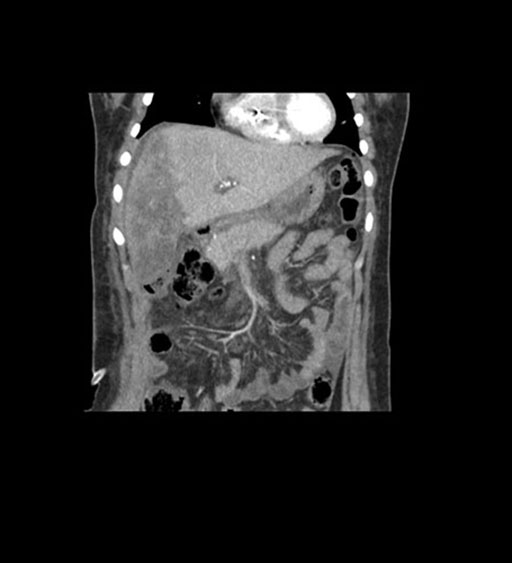

Coronal Arterial

Imaging analysis

Based on initial findings, which issue(s) would you be most concerned about?